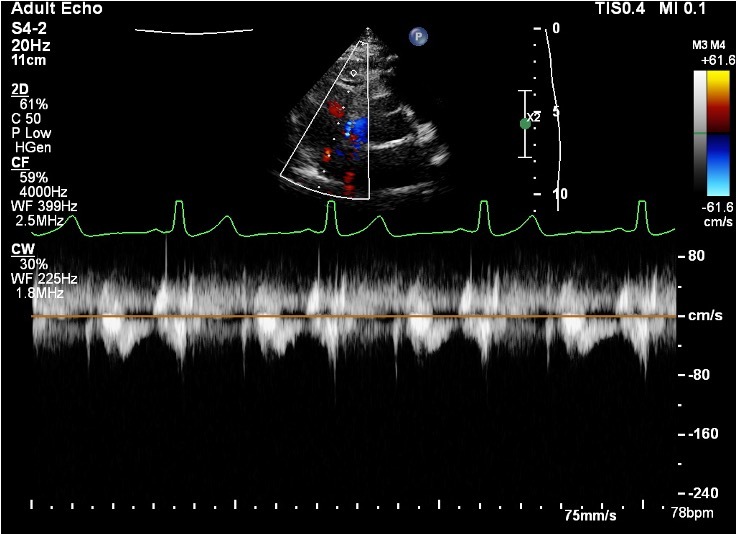

10

Q

Should we measure this TR?

A

No because we would be guessing. See how the furies is right in the blue jet?